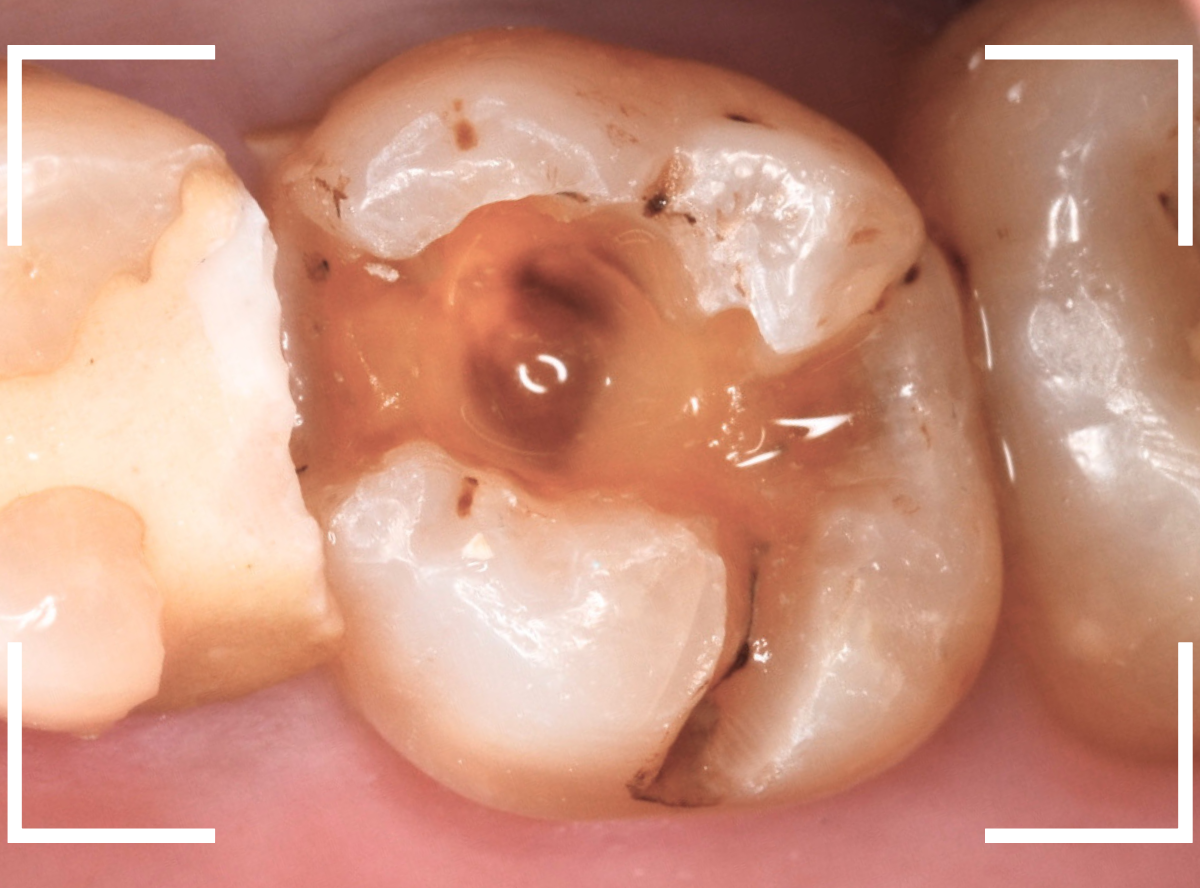

今回は、奥歯が神経に達する虫歯になってしまった患者さんのケースです。

隣りの歯とのすき間に大きな穴が空いているのが見えます。

レントゲン写真で確認します。

金属のつめものの下が、神経まで達する大きな虫歯になっています。

麻酔をして神経の治療をします。

さて、神経の治療が終わり、歯の土台を作ったところで、手前の歯の側面にも虫歯が見つかり、治療を始めました。

手前の歯の虫歯も金属の中まで虫歯になっていました。

手前の歯の虫歯もかなり広い虫歯でした。